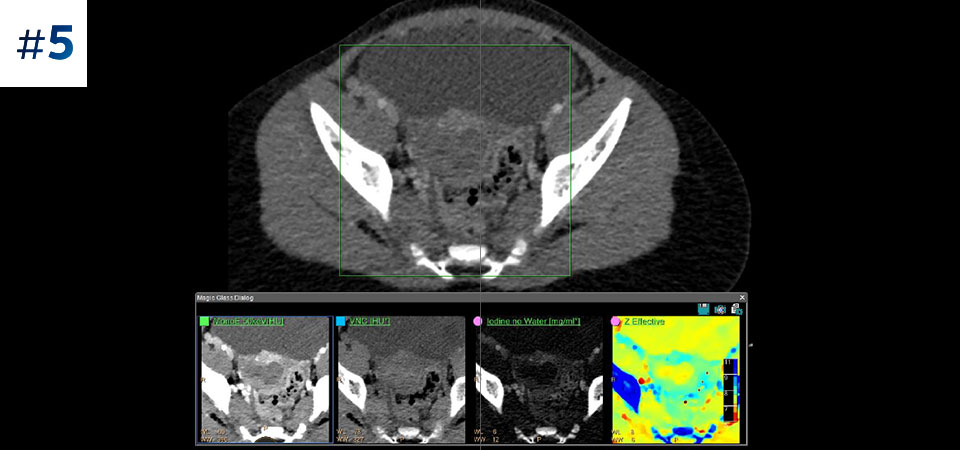

Allez au-delà de la TDM classique. Découvrez de quelle manière des couches de résultats issus de scanners à détection spectrale peuvent améliorer la fiabilité de votre diagnostic.

Observez la différence entre le scanner à détection spectrale et le scanner classique

Découvrez les avantages du scanner à détection spectrale